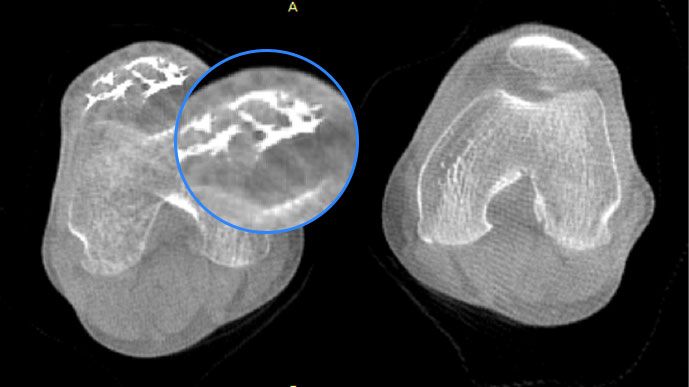

膝關(guān)節(jié)

精準(zhǔn)診斷

手術(shù)方案規(guī)劃

術(shù)后隨訪(fǎng)